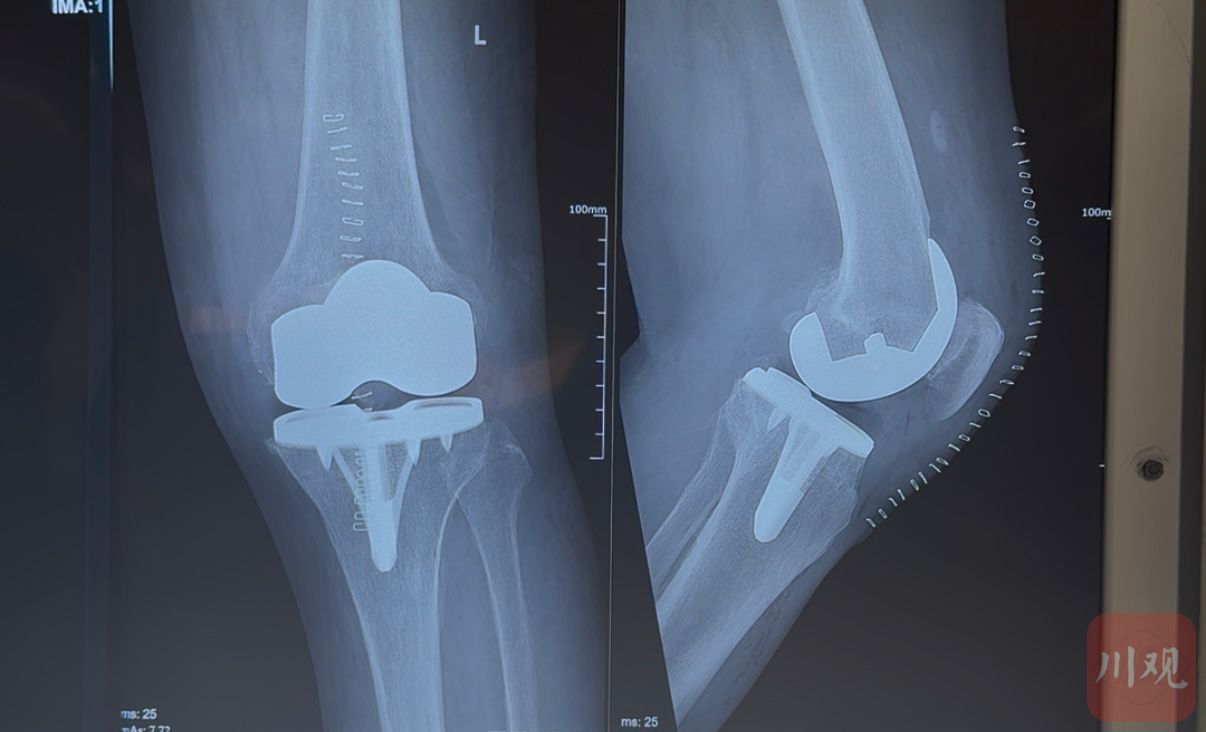

“我们现在给大骨节病患者装入个性化设计的‘股骨假体 + 胫骨假体 + 含维生素E的高交联聚乙烯内衬’这三件套,实现‘行走自如不松动’。”周宗科指着模型四说,术后患者能行走、能干活,甚至还可以去爬峨眉山。

股骨假体+胫骨假体+内衬三件套。魏冯 摄